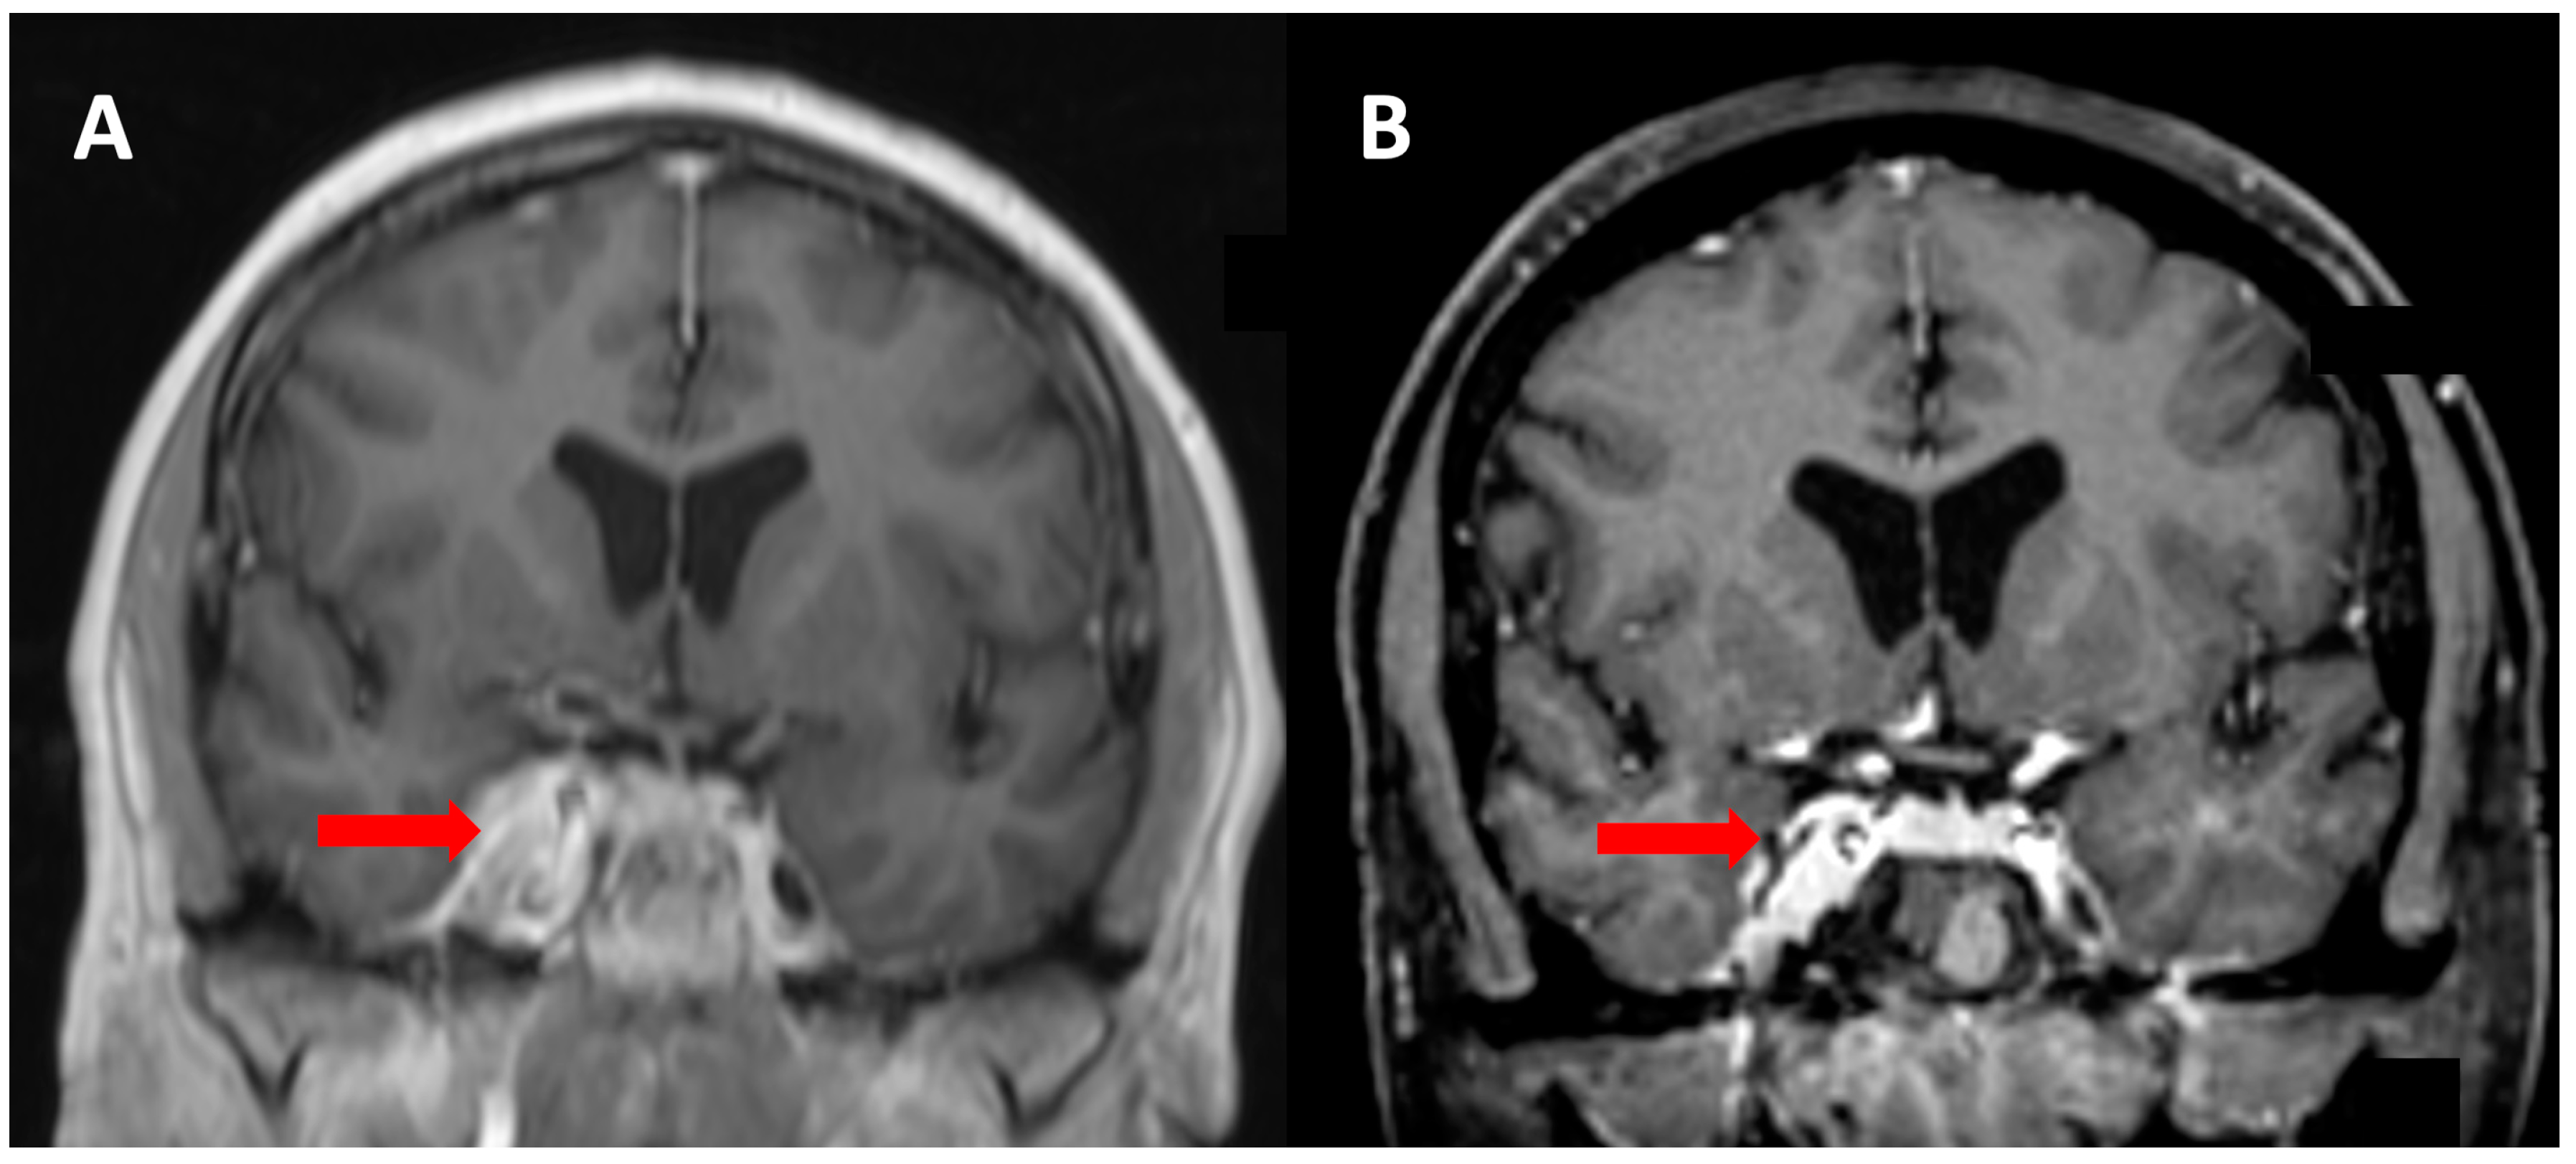

Illustrative Case Report